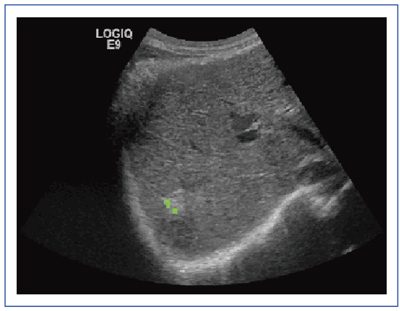

腹部超音波テキスト 上・下腹部 改訂版 ベクトル・コア - メルカリ。腹部超音波テキスト〜上・下腹部〜 改訂第三版 (Atlas Series超。腹部超音波テキスト〜上・下腹部〜 改訂第三版 (Atlas Series超。未開封★サブレミシェル ケーキサブレ缶15個入り。腹部超音波テキスト : 上・下腹部 本。楽天市場】日超検 腹部超音波テキストの通販。腹部超音波テキスト 上・下腹部 改訂版 ベクトル・コア - メルカリ。美品】腹部超音波テキスト : 上・下腹部 改訂第3版。一般社団法人日本超音波検査学会 eラーニング。2025年最新】腹部超音波テキスト 上 下腹部の人気アイテム。大きな超音波,小さな超音波- GEヘルスケア・ジャパン株式会社。スタンダード腹部超音波診断 | 森 秀明 |本 | 通販 | Amazon。腹部超音波検査」特集スライド(金本英之先生) | VETS TECH。表紙に筋あとがありますが書き込み、印などなく綺麗です。